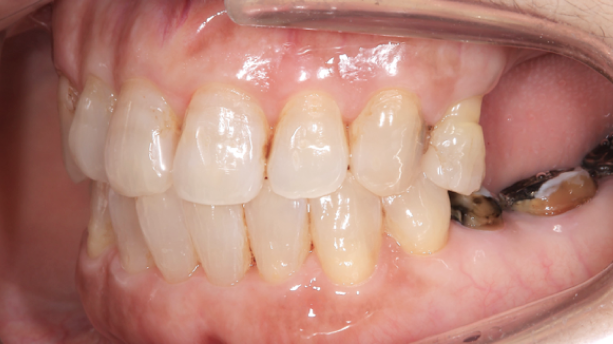

この歯(黄色の印)は顎を横に動かした時に強い力が加わり、歯の周囲の組織にダメージが出ているため、力をコントロールするために歯の形を修正が必要です。

右の奥歯についても歯が伸びてしまっているのでこちらは部分的な矯正治療と歯茎の手術で対応しています。